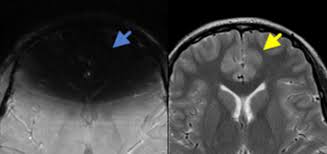

Radiology Quiz Urology News

Radiology Quiz Urology News from www.urologynews.uk.com